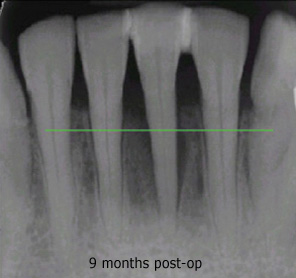

As the gums heal, the teeth will shift, and your bite will need to be adjusted several times over the first few weeks, even for the first year and beyond. Although it seems counter-intuitive, inadequate adjustment is what is usually responsible for soreness or sensitivity following LANAP.

Professional cleaning is recommended every three months for the first year, and re-evaluation of your condition will be done at the twelve month visit. Most people with gum disease remain at risk for the rest of their lives, and would benefit from having their teeth cleaned every three months indefinitely.